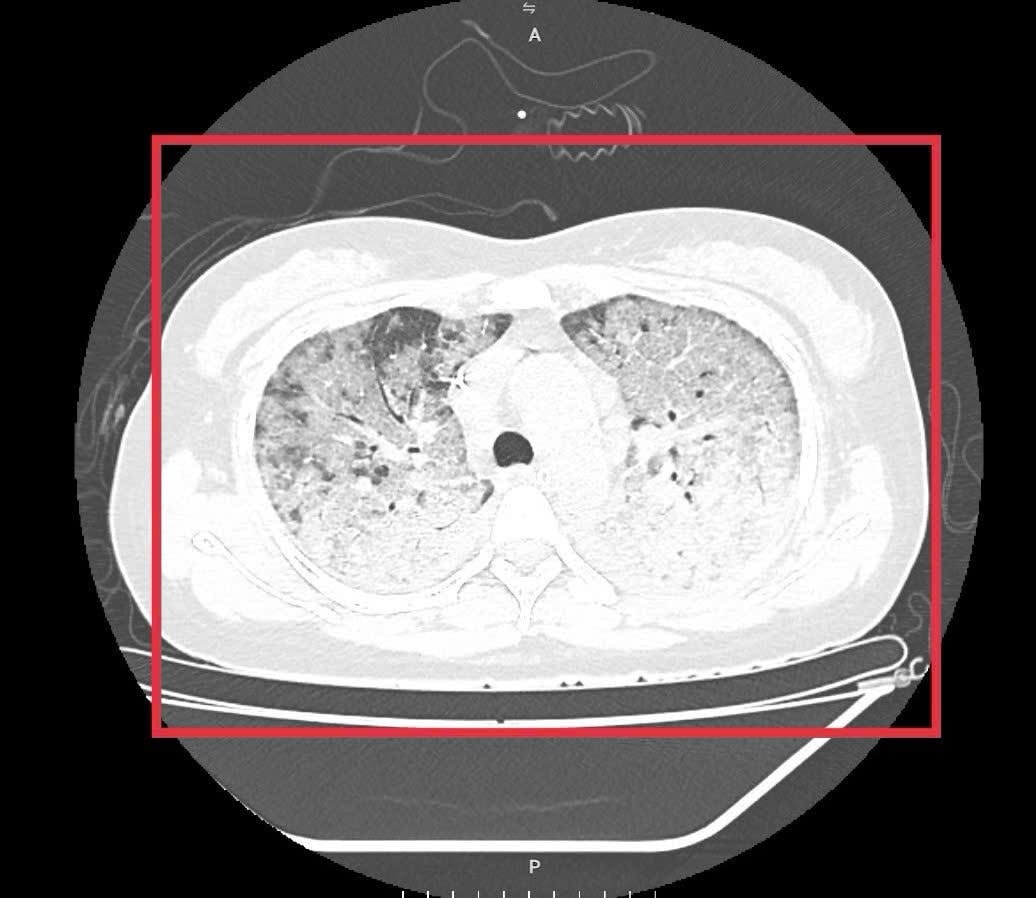

Hình ảnh chụp X-quang và CT phổi cho thấy tổn thương lan tỏa hai bên phổi, hình ảnh kính mờ điển hình của cúm tiến triển, nhanh chóng chuyển sang hội chứng suy hô hấp cấp (ARDS) - biến chứng nặng thường gặp ở bệnh nhân suy giảm miễn dịch.

Hình ảnh X-quang phổi cho thấy tổn thương lan tỏa hai bên phổi do cúm mùa tiến triển. Ảnh: BVCC